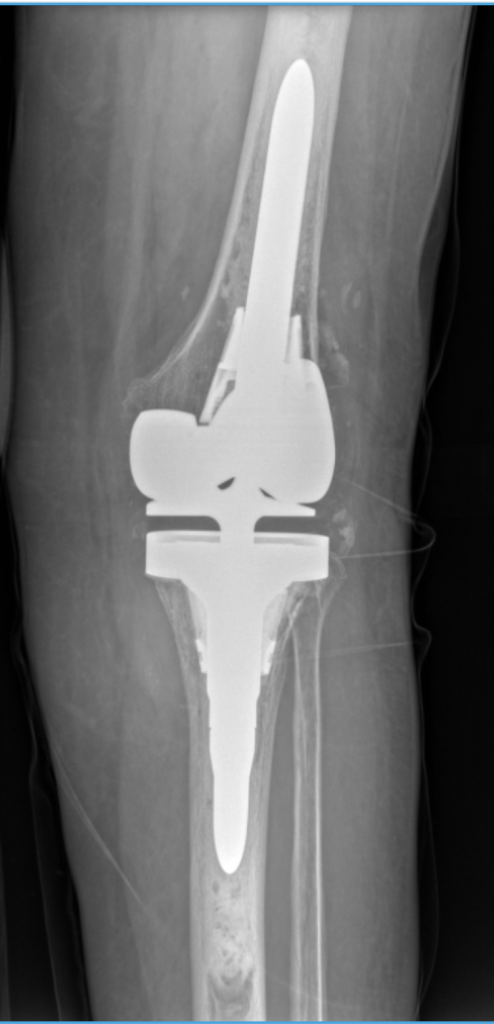

Sometimes a previous hip or knee replacement may wear out, loosen, or become infected over time. When that happens, a revision joint replacement is required to restore stability and function. Dr. Kamran Movassaghi specializes in complex revision surgery for patients throughout Pasadena, CA, and the surrounding region.

Dr. Movassaghi removes the failing implant, repairs or rebuilds any damaged bone, and places a new, custom-fitted implant designed for durability and stability. These complex procedures require advanced training and precision planning, which Dr. Movassaghi provides through his fellowship expertise.